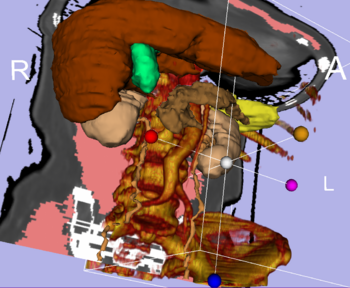

Integrated Volume Rendering: View of the abdominal atlas Bone and large vessels are volume rendered. |

Volume Rendering: Fully integrated volume rendering with cropping for easy exploration of volumetric data